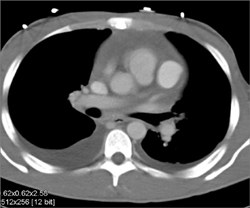

Diagnosis

Stent in RCA